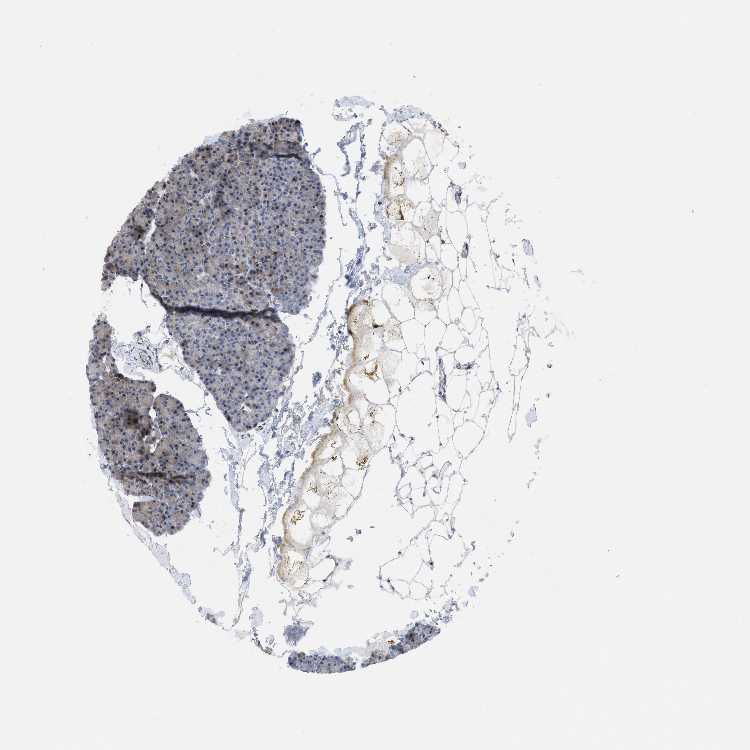

PANCREAS - Antibody stainingi

Antibody staining in the annotated cell types in the current human tissue is reported as not detected, low, medium, or high, based on conventional immunohistochemistry profiling in selected tissues. This score is based on the combination of the staining intensity and fraction of stained cells.

Each image is clickable and will lead to virtual microscopy that enables deeper exploration of all samples and also displays staining intensity scores, fraction scores and subcellular localization as well as patient and tissue information for each sample.

Antibody HPA019011

Exocrine glandular cells Medium

Pancreatic endocrine cells Low